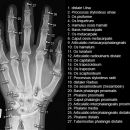

Handgelenk a.p.

Beurteilungskriterien

- Neigung der distalen Radiusgelenkfläche in der Frontalebene: 15 – 35°

- Längenverhältnis Radius – Ulna: Proc.styloideus radii überragt Gelenkfläche der Ulna um 9 –12mm (<9mm Ulna-Plusvariante, >12mm Ulnaminusvariante)

- Kontinuität der drei Karpalbögen:

Proximaler Bogen: proximale Gelenkflächenkonturen von Scaphoid, Lunatum und Triquetum

Mittlerer Bogen: distale Gelenkflächenkonturen von Sacphoid, Lunatum und Triquetum

Distaler Bogen: proximale Gelenkflächenkonturen von Capitatum und Hamatum

Fehlende Abgrenzbarkeit, Versatz oder Unterbrechung sind als pathologisch zu bewerten und deuten auf eine Luxation hin.

Trapezförmige Darstellung des Lunatum in Neutralstellung? Augenzeichen des Hamulus? Superposition von Pisiforme und Triquetum? Metacarpale III in Projektion innerhalb der Radiusgelenkfläche? Lunatum zu >50% über Radiusgelenkfläche? Cave: bei Radial- oder Ulnarduktion wandert das Lunatum in umgekehrter Richtung.

- M-förmiger Verlauf der Gelenkspalten der Carpometacarpalgelenke? Luxationsstellung in den Carpometacarpalgelenken (meist dorsale Luxation)?

- Gelenkspaltweiten des Radiocarpalgelenk 2 – 2,5mm, der Carpometacarpalgelenke 1 –2mm, distales Radioulnargelenk 2mm, Gelenksspaltweiten der Intercarpalgelenke 1,5 – 2mm

Cave: SL-Dissoziation (Ruptur des SL- Bandes, häufigste Gefügestörung): Terry-Thomas-Sign = SL-Spalt > 3mm, Siegelringzeichen = Ringförmige Transparenzminderung im mittleren Scaphoiddrittel durch orthograde Projektion der Taille infolge Rotation.

- Obliteration des Scaphoidfettstreifens?

- Täuschungsmöglichkeiten durch Vielzahl akzessorischer Ossikel (abgerundete, zirkulkär-geschlossene Kortikalis), geteilte Handwurzelknochen (Scaphoid, Lunatum, Pisiforme) und Gefäßkanälchen

- Target areas leicht zu übersehender Frakturen: distales Radioulnargelenk, Processus styloideus radii et ulnae, Basen der Metacarpalia (v.a. MCP I), Hamulus.

- Grundsätzlich gilt: unklare Verhältnisse ->CT-Indikation